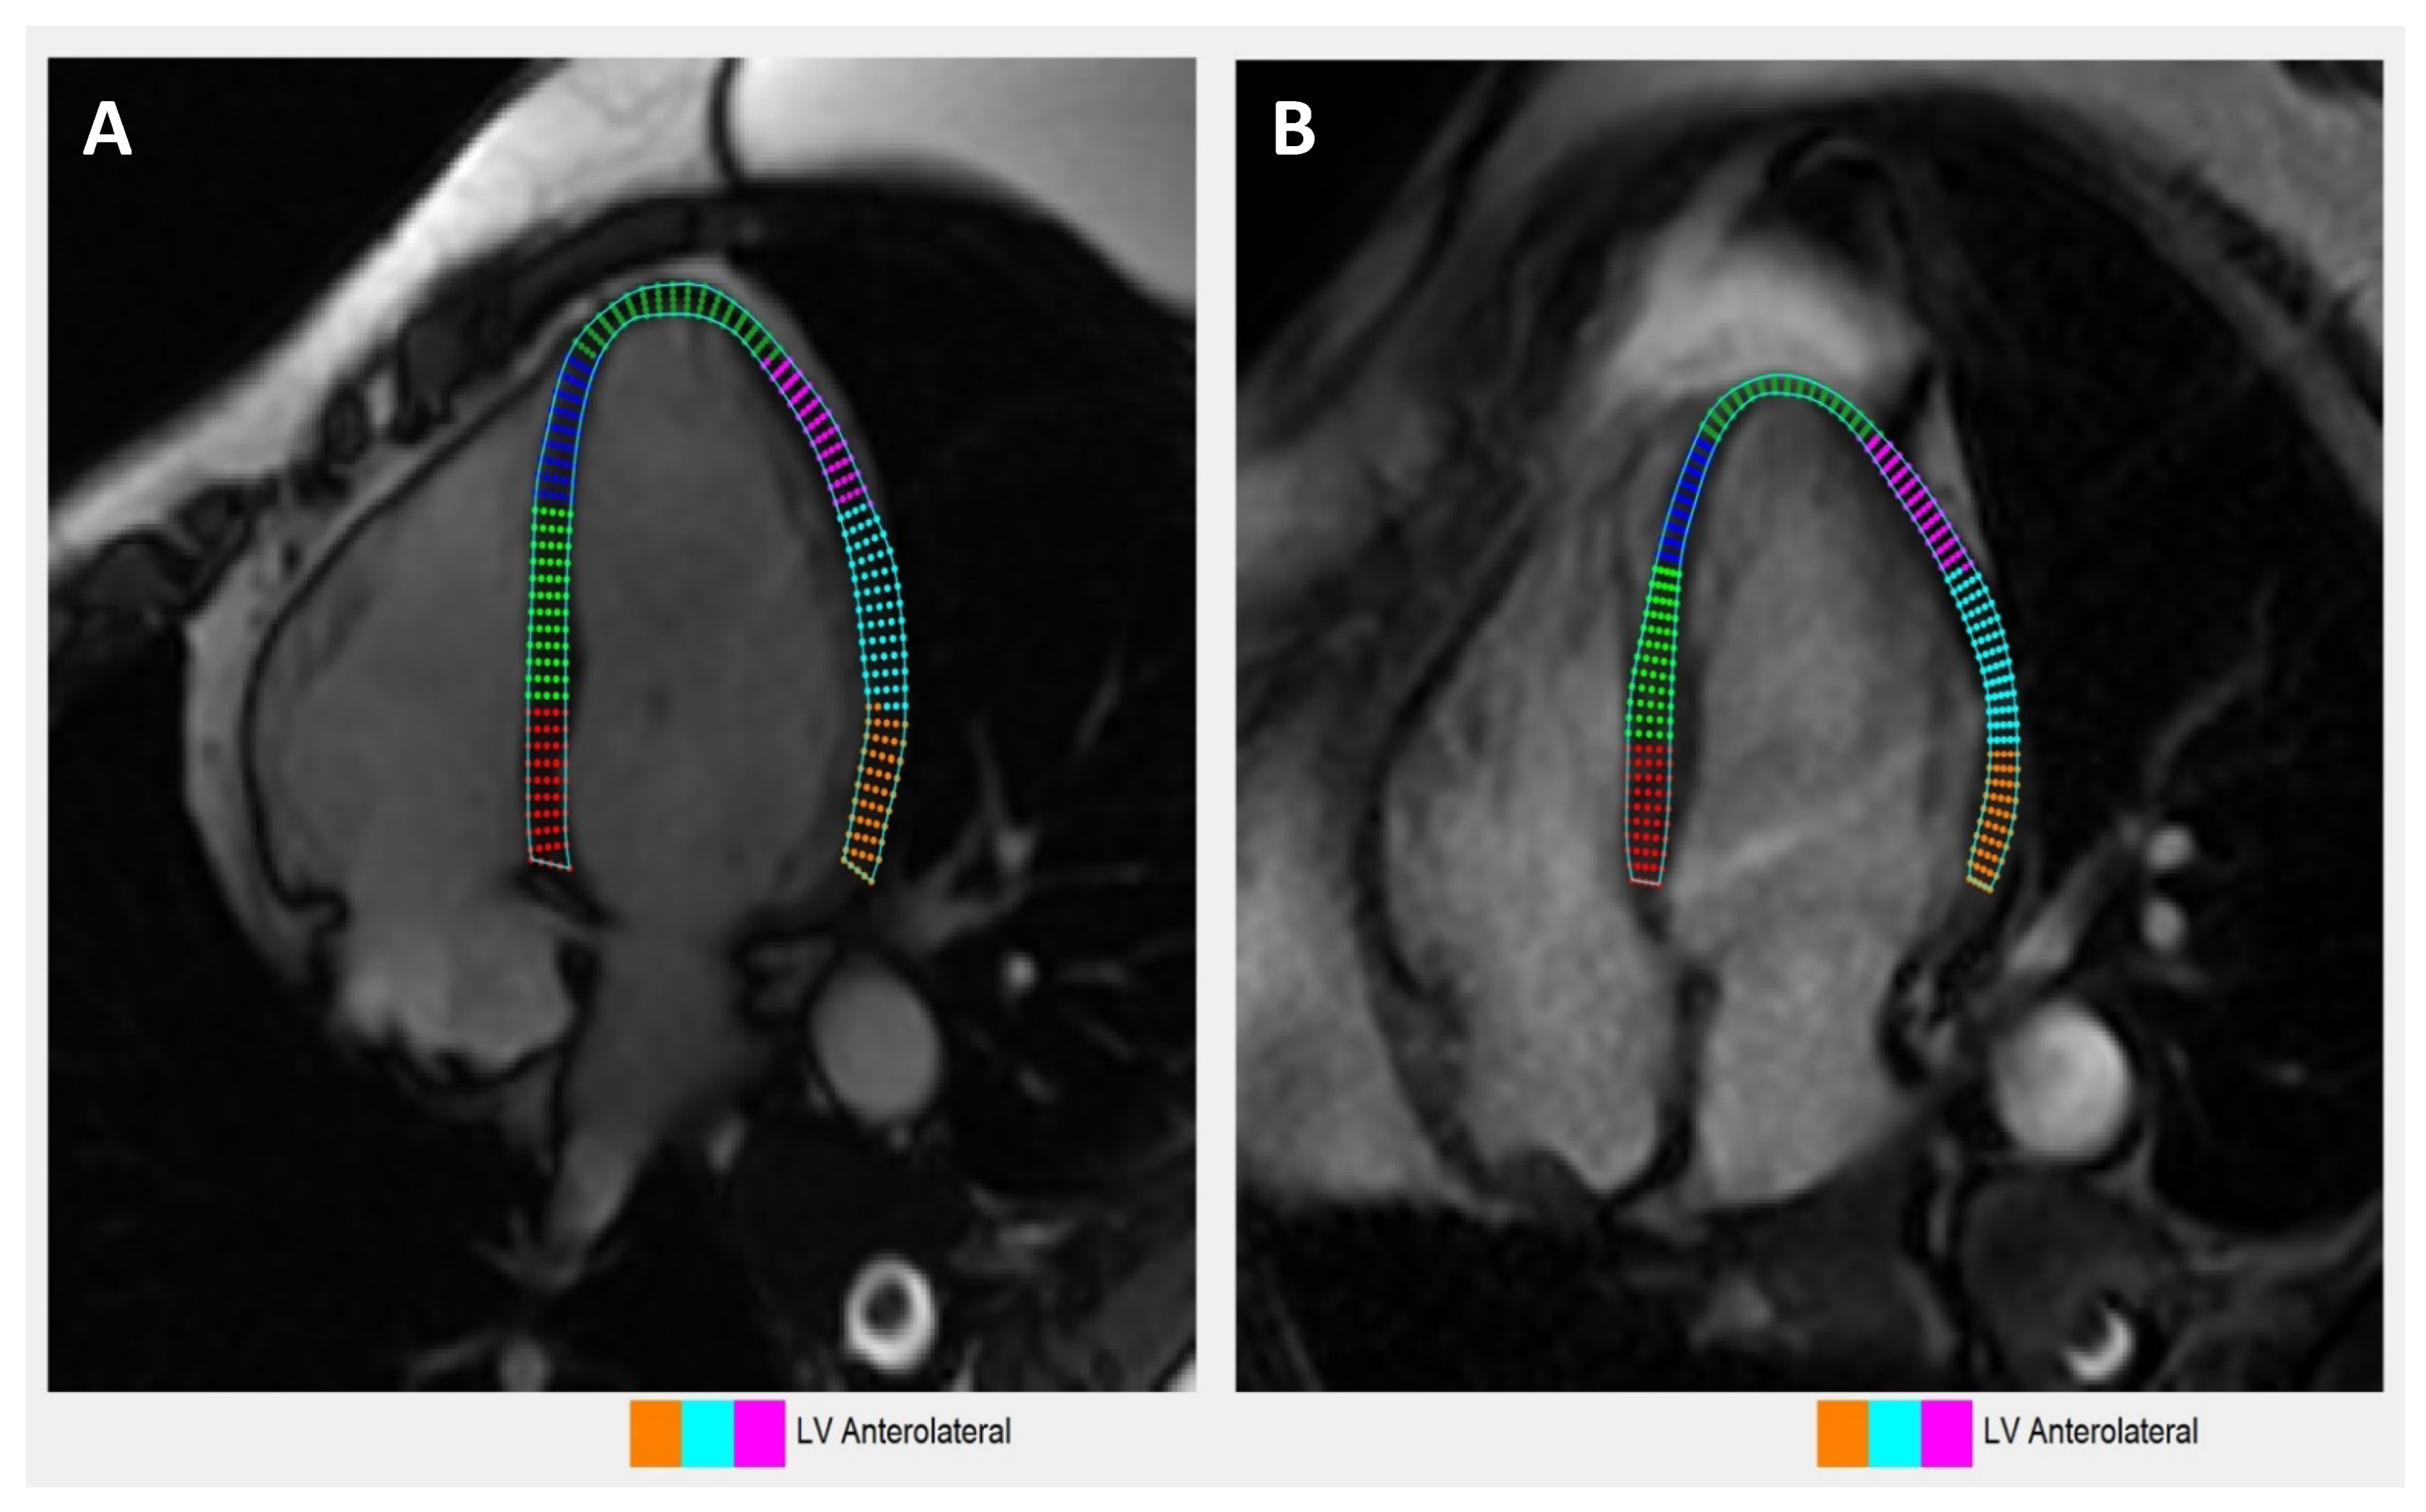

2.5. Contrast-Enhanced CMR Protocol

3.7. Cardiac MRI Characteristics

3.8. Comparison of Echocardiography vs. Cardiac Magnetic Resonance Imaging-Based Strains